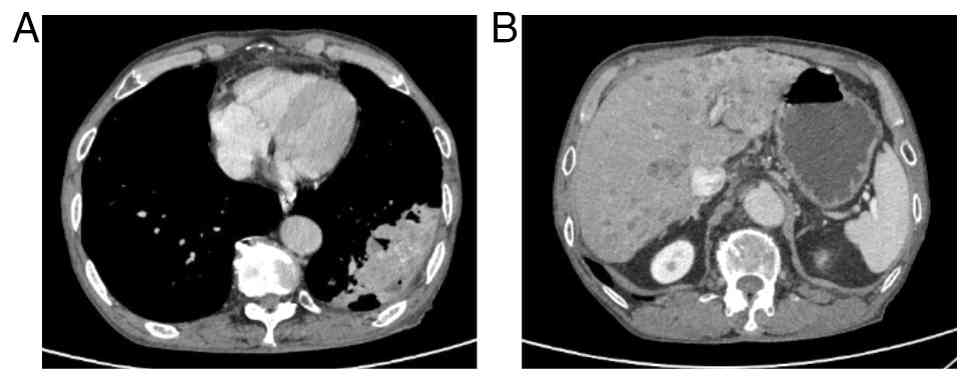

In June 2024, a 74-year-old man was admitted to Huai'an Hospital Affiliated to Yangzhou University and The Fifth People's Hospital of Huai'an (Jiangsu, China) with symptoms of coughing, hemoptysis, decreased appetite and abdominal distension. The patient had a history of chronic obstructive pulmonary disease spanning over 20 years. Computed tomography (CT) identified a 12.3-cm soft-tissue mass in the left lower lobe of the lung, with multiple metastatic lesions noted in the liver (Fig. 1). A biopsy of the lung lesion under CT control was performed. Tissues were fixed in 10% neutral formalin solution at room temperature for 24 h, then dehydrated and embedded in paraffin. The tissues were sliced into 5-µm thick sections. Immunohistochemical analysis was performed using the EnVision two-step method. Both primary and secondary antibodies were ready-to-use antibodies purchased from Henan Celnovte Biotechnology Co., Ltd. The following antibodies were employed: CK5/6 (clone C6H1/C1C8; catalog no. CCM-0983), p40 (clone C3B4; catalog no. CPM-0133), p53 (clone C2H10; catalog no. CPM-0142) and Ki-67 (clone C3G4; catalog no. CKM-0032). All staining was performed using an automated immunohistochemical staining machine (catalog no. CNT360-M2; Henan Celnovte Biotechnology Co., Ltd.), according to the manufacturer's instructions. All section observations and image acquisition were performed using a light microscope (ECLIPSE Ci-S; Nikon Corporation). Immunohistochemical analysis of the tissue sample revealed positive expression of CK5/6, p53 and p40, and the Ki-67 index was 30% (Fig. 2). Based on clinical presentation, imaging studies and pathological findings, the patient was diagnosed with primary lung squamous cell carcinoma. The patient refused a liver biopsy and programmed death ligand 1 testing. The patient was diagnosed with squamous cell carcinoma of the left lower lung lobe and liver metastasis, cT4N3M1c, clinical stage IVB, according to the American Joint Committee on Cancer 8th edition (13). The patient received intravenous sintilimab (200 mg on day 1) and albumin-bound paclitaxel (200 mg on day 1 and 100 mg on day 8) plus cisplatin (30 mg on days 1–3) of each 21-day cycle for 4 cycles. In October 2024, the patient showed a significant reduction in measurable lesions with regard to both the primary tumor and liver metastasis. The mass in the lower lobe of the left lung decreased from 12.3 to 8.4 cm in diameter, while the largest liver metastasis shrank from 3.8 to 1.5 cm in diameter, with some liver metastases disappearing (Fig. 3). Following the aforementioned four cycles of sintilimab and albumin-bound paclitaxel plus cisplatin, the patient continued maintenance therapy with sintilimab (200 mg on day 1 of each 21-day cycle). Tumor status was assessed every 6 to 8 weeks. The assessment included CT scans of the chest, abdomen and pelvis. In June 2025, CT demonstrated a nodular contour of the liver with capsular retraction, mild ascites, and esophageal and gastric varices (Fig. 4). The patient had no history of alcohol consumption. Laboratory tests indicated negative or normal results for all causes of liver disease, including serological tests for hepatitis B and C, and serological tests for autoimmune conditions. The patient refused to undergo a liver biopsy. The patient's alanine aminotransferase level was 57 U/l (normal range, 9–50 U/l), aspartate aminotransferase was 55 U/l (normal range, 15–40 U/l), γ-glutamyl transferase was 185 U/l (normal range, 15–40 U/l), total bilirubin was 27.9 µmol/l (normal range, <26 µmol/l) and albumin was 29.4 g/l (normal range, 40–55 g/l). The patient underwent abdominal paracentesis, with large-volume drainage of ascites, diuretic therapy and infusion of human albumin (once daily, 10 g per dose) as part of active treatment. Over the next 2 months, the Eastern Cooperative Oncology Group (http://ecog-acrin.org/resources/ecog-performance-status/) performance status gradually worsened. In August 2025, the patient ultimately succumbed to hepatic failure.

Computed tomography scans showing (A)

the left lower lobe mass decreased to a maximum diameter of 8.4 cm.

(B) Multiple liver metastases decreased, some completely

disappearing.

Figure 3.

Computed tomography scans showing (A) the left lower lobe mass decreased to a maximum diameter of 8.4 cm. (B) Multiple liver metastases decreased, some completely disappearing.